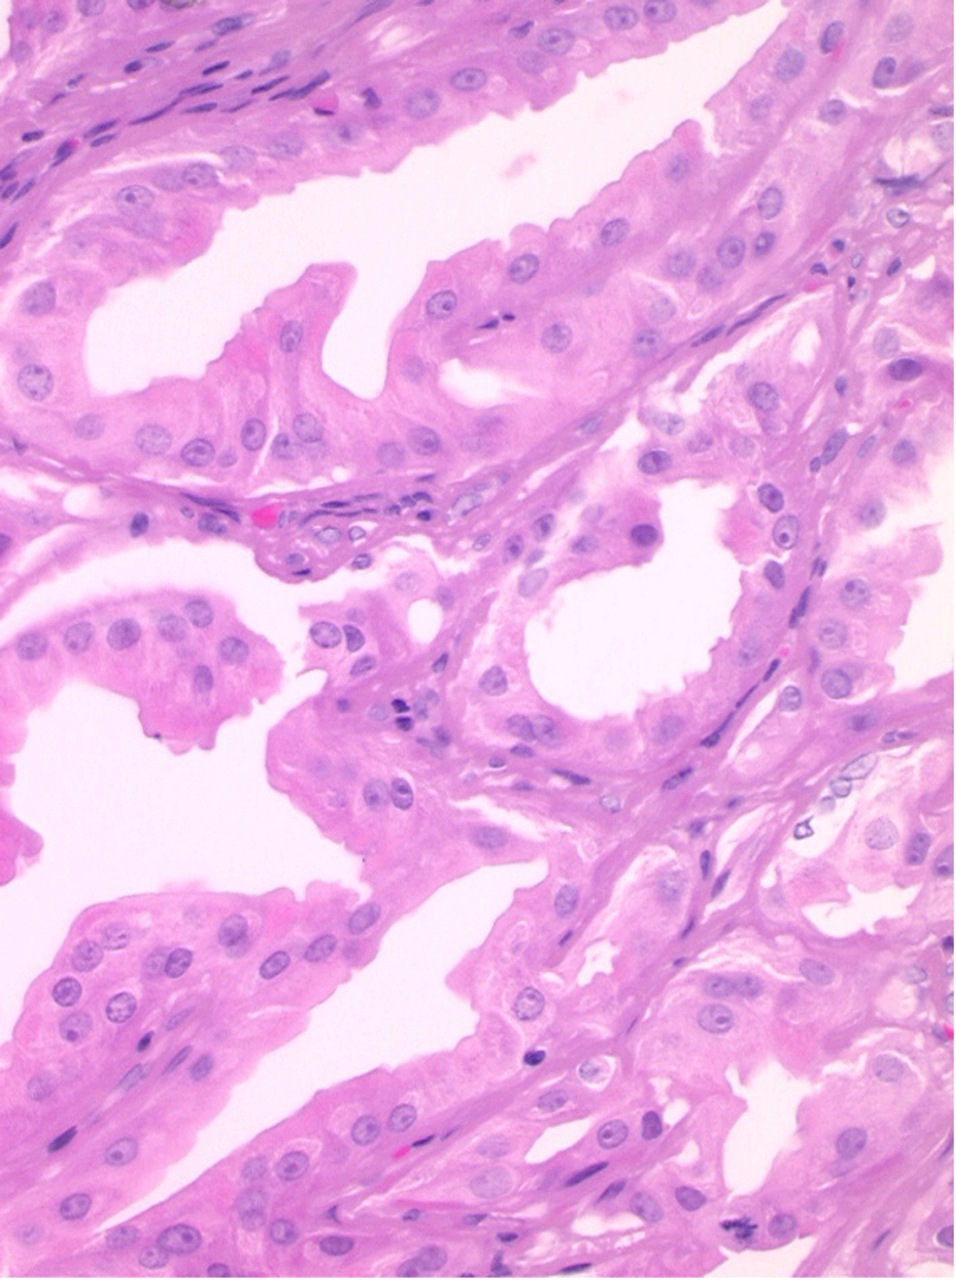

Une femme de 31 ans consulte pour une « boule » périanale ancienne et indolore mais inesthétique. L’examen clinique révèle une tuméfaction rosée de la marge anale (fig. 1).

L’hidradénome papillifère est habituellement asymptomatique ; de rares douleurs et/ou saignements peuvent survenir en cas d’érosion de la surface. Le plus souvent, il prend l’aspect d’un nodule intradermique rond, unique, ferme, mobile, recouvert par une peau normale, de couleur rose, translucide, généralement de petite taille. Parfois, il a un aspect bleuté, exophytique et/ou ulcéré. Le diagnostic repose sur l’analyse histologique (fig. 3).